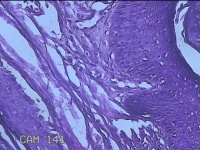

左眼外侧缘上肿物

性别

女

年龄

60岁

临床诊断

痣;疣

左眼上睑缘白色丘疹1年余。

灰白粉红色肿物0.8x0.3x0.2cm两个,表面光滑。

图2